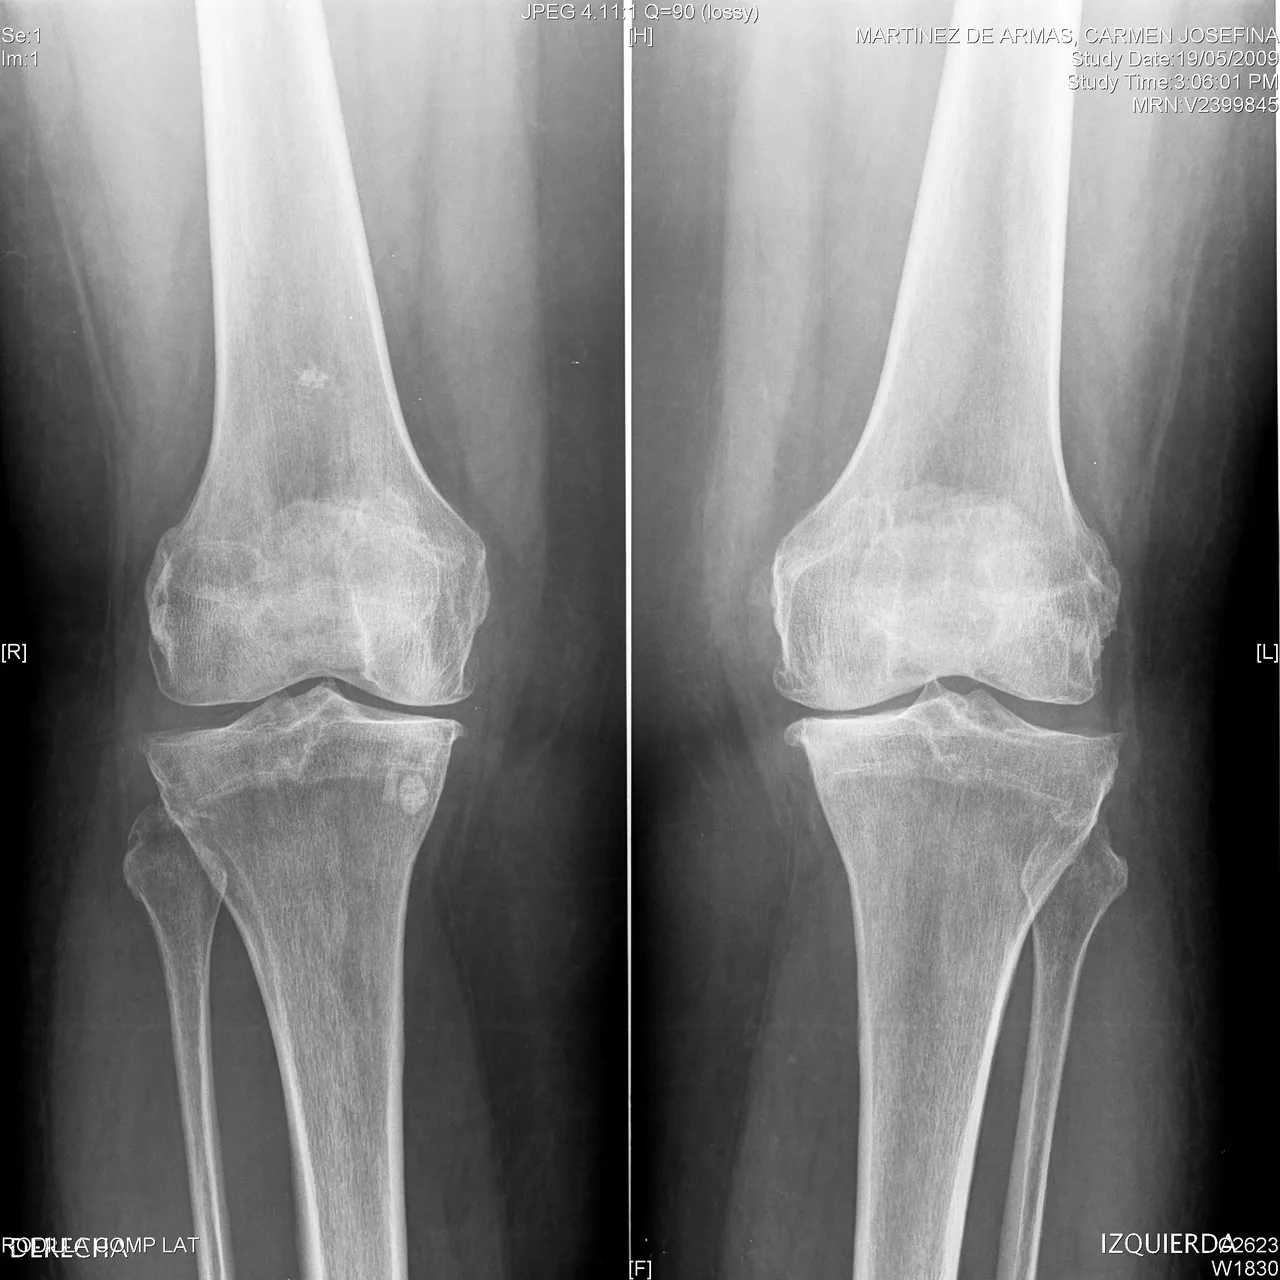

Bilateral degenerative pathology in the knees is very frequent and incapacitating. The management offered in advanced cases is prosthetic replacement. The knee undergoes mechanical and degenerative changes with age, the particular activity of each person, their physical characteristics and, added to this, chronic diseases.

People in the sixth decade of life continue to be the most affected, since due to their lack of activity, they offer less resistance to knee wear, which alters their normal physiological axis and causes severe angular deformities.

Bilateral affection and severe knee pain are common and their treatment may be timely, total, definitive and bilateral; however, the costs involved in bilateral knee replacement are high and inaccessible to most people. In such a case, it is often chosen to offer palliative treatments, inexpensive and allowing the activities of the patient.